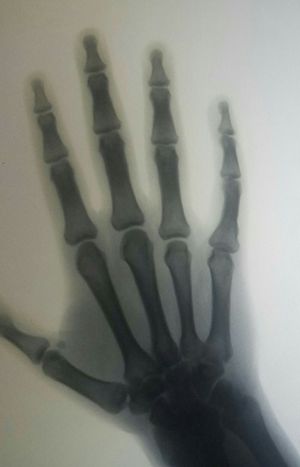

Pinky disorder

Decreasing articular space in PIP and metocarpophalengeal space.

Decrease in space in pip it lead to pain in movement of finger best treat may be physiotherapy 🤔